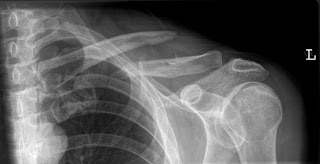

Results: Operative fixation of mid-shaft

clavicle fractures increased by 368% and by 349% in California and New York,

respectively, while the number of patients with clavicle fractures presenting

to emergency departments remained stable.